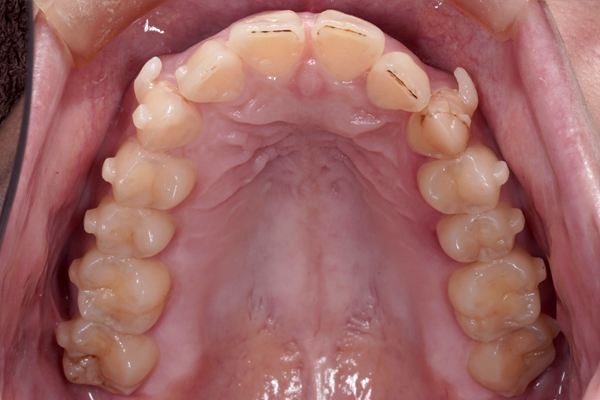

上の歯の比較(咬合面)

下の歯の比較(咬合面)